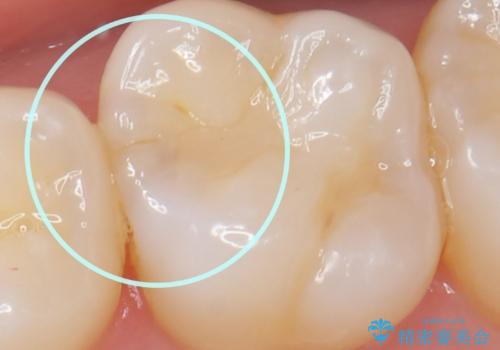

虫歯の発生を初期段階で発見 ゴールドインレー修復

- メンテナンス・検診で数ヶ月に一度定期的に来院されている方の治療例です。

定期的にX線写真を撮影しチェックすることで、外から見てわかるプラークコントロールだけでなく虫歯を初期段階で発見し対策することができます。

歯ぎしりの癖があることから強度に優れるゴールドインレーにて修復を行いました。